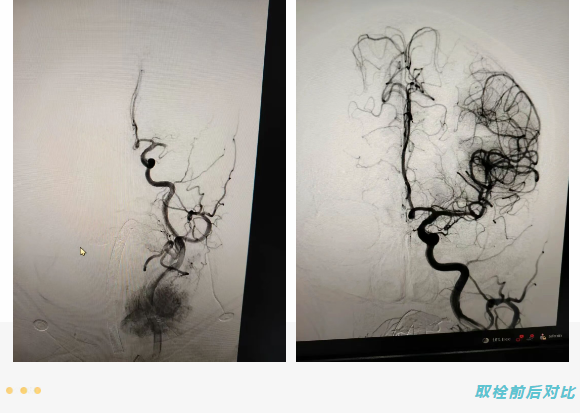

入院时,患者病情持续进展,意识障碍加重。神经内一科接诊后,结合影像学检查结果,明确诊断为“左侧大脑中动脉闭塞脑梗死”。由于患者发病时间不明确,不符合静脉溶栓条件,但头颈部CTA与CTP评估显示,存在明确急诊介入取栓治疗指征。

手术过程顺利,仅用59分钟便成功实现血管再通,取出堵塞血栓。术后患者转入ICU接受进一步生命支持与综合治疗。次日,患者神志转清,病情稳步改善。经ICU、神经内科相继治疗后,现已康复出院。